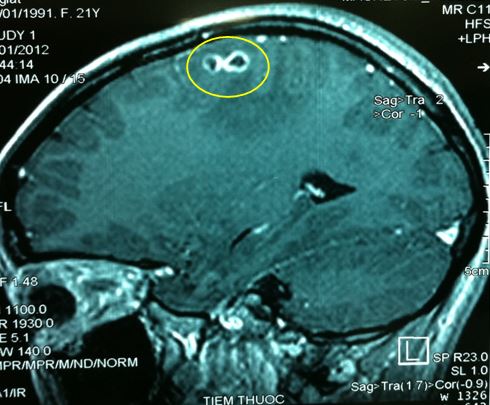

Hình ảnh MRI : tổn thương tại thùy đỉnh phải, ngấm thuốc dạng viền và có phù não xung quanh.

Kết luận của chẩn đoán hình ảnh: theo dõi tổn thương do Toxoplasma.